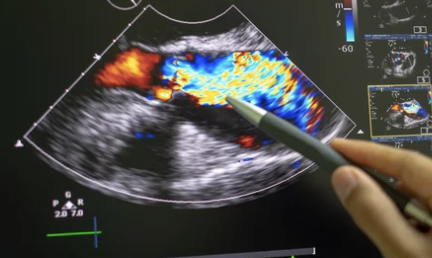

✏️ 이 경우 정기적인 심전도 검사나 심장초음파 등 건강검진이 중요하며, 가족력이 있는 경우 더 적극적인 관찰이 필요합니다.

| 심장초음파 | 심장 기능 및 구조 확인 |